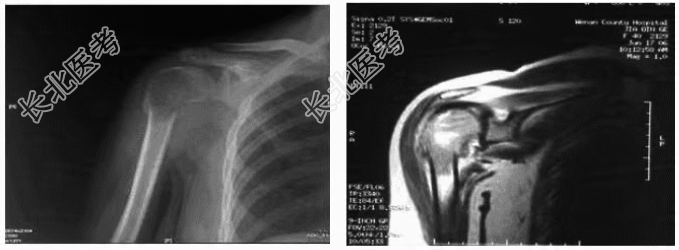

- [材料题] 患者女性,39岁,一月前打羽毛球时扭伤右肩关节,伤后右肩关节疼痛、反复肿胀、活动受限,经理疗、膏药、口服消炎止痛药物治疗效果不明显,1天前提重物(约10公斤)后疼痛加重,肩关节不能活动。体检:右肩关节轻度肿胀,皮肤无淤斑,肩关节周围压痛,肩关节各方向活动受限。

- 多项选择题2.肩关节X线片所见。根据肩关节X线片,你认为该病人诊断应考虑哪些

- 多项选择题4.肩关节MRI所见,血常规、血碱性磷酸酶正常, 肝胆胰脾肾B超、胸部平片和CT检查均未发现异常,穿刺活检病理报告为“骨巨细胞瘤”。根据Enneking分期系统, 该患者应为